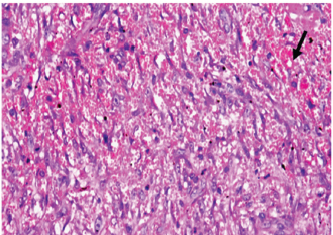

At 7 days post wounding; the inflammatory reaction was moderate and characterized by polymorphonuclear cells and macrophages infiltration with the presence of small scab covering the wound surface. Early evidence of epithelization was detected and represented by the proliferation of epidermal epithelium under the scab. There was marked thickening and hyperplastic proliferation of epidermal epithelium at the free wound edge (Fig. 6). The dermal tissue underlying the wound area showed few polymorphonuclear cells infiltration and more abundant mononuclear cells. Fibroplasia and angiogenesis were detected in the dermis and more extensive in deeper areas of the dermis which characterized by fibroblast and angioblast proliferation forming immature young granulation tissue (Fig. 7). At 14 days post wounding, the wound area was covered by a complete layer of epidermal epithelium indicating a good epithelization rate of the wound. Proliferation of cutaneous appendages was detected. The newly formed epithelium was thick and showed partial keratinization and epithelial differentiated stratum containing polyhedral keratinocyte with the appearance of keratohyalin granules in their cytoplasm (Fig. 8). The dermal tissue showed deposition of parallel well organized and interconnected collagen bundles that arranged parallel to epidermis associated with enhanced angiogenesis represented by well-developed blood capillaries (Fig. 9). At 21 days post wounding, remodeling of the formed epithelium with relatively small scar formation and mild restoration of skin appendages. Keratinized and differentiated stratum comprising the covering epithelium and the newly formed skin appendages from the basal epidermal epithelium were detected (Fig. 10). The dermal tissue revealed well-formed organized tissue consisted of parallel compact and interconnected bundles of collagen with scant angiogenesis (Fig. 11). At 28 days post wounding, well-formed scar tissue covering highly cellular organized tissue was detected (Fig. 12). The dermal tissue revealed well-arranged compact collagen bundles containing scarce blood vessels (Fig. 13).

Fig. 11. Skin of a goat from electroacupuncture group at 21 days post wounding showing well-formed organized tissue consisted of parallel compact and interconnected bundles of collagen with scant angiogenesis (arrow head) (HE ×200).